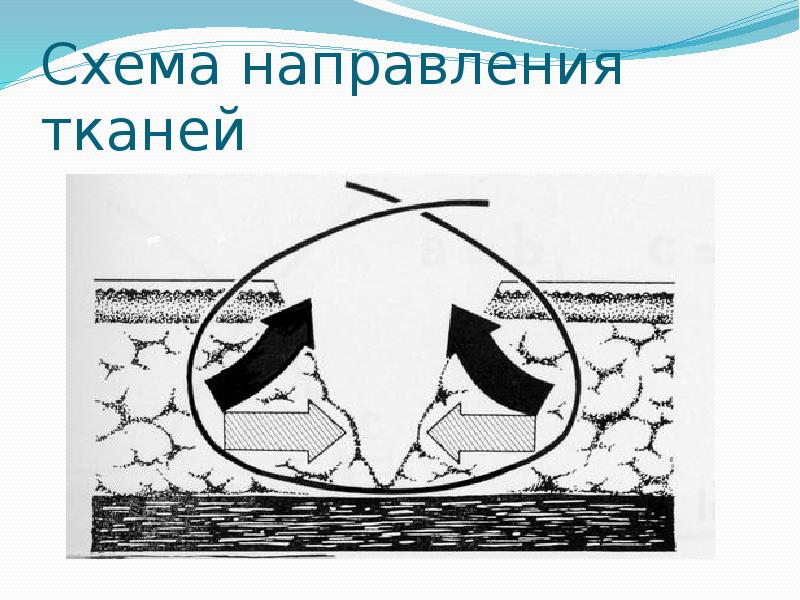

- 21. Схема направления тканей